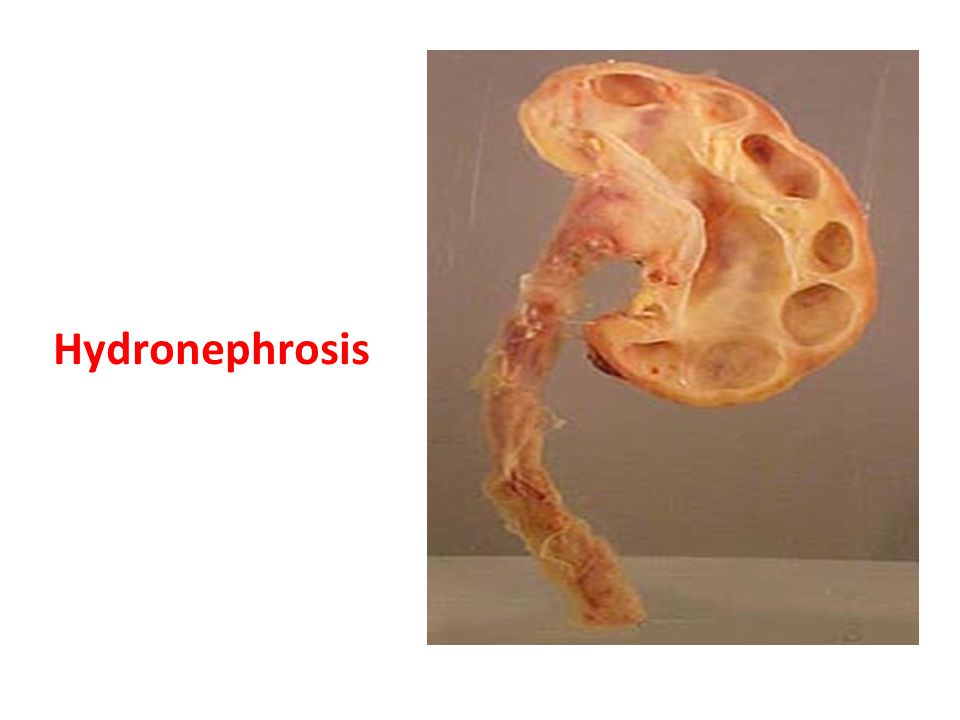

Интраренальная лоханка: рентгеновские снимки и примеры

Раздел: Фотоэссе